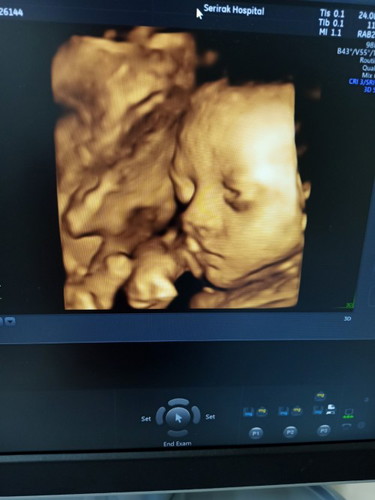

สอบถามแม่ๆ ช่วยดูว่าน้อง ปาก ปกติมั้ยค่ะ กลัวน้องเป็น ปากแหว่ง แต่หมอบอก ปกติ หรือแม่คิดไปเอง